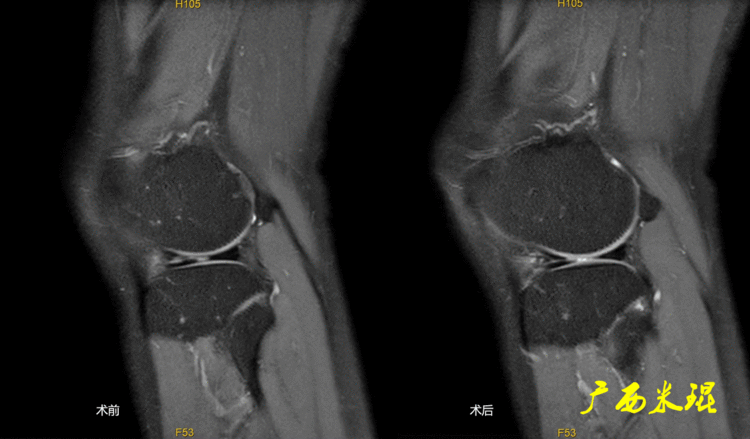

14、手术后半月板半月板手术后导致的半月板形态和信号的改变千变万化,有时候其改变可能在MR上比手术前还差,这种MR上的改变不代表手术存在问题,所以已故的冯华教授生前就经常说手术后的半月板MR很难评价。

下面矢状位MR是外侧半月板后角部分切除手术后,片上我们发现半月板后角部分缺失,半月板信号正常(因为手术前半月板没有退变)。

下面矢状位MR是内侧半月板后角水平撕裂部分切除手术后,半月板后角部分缺失,信号仍然不正常(因为手术前半月板已经有退变),真正的情况是关节镜下半月板外观是正常的,MR上看见的高信号影是半月板退变的Ⅱ级信号所致,由于手术切除面达退变的层面,MR上容易误诊为Ⅲ级信号。

下面矢状位MR是内侧半月板后角纵形撕裂缝合手术后,半月板外观完整,无分离,缝合处小片状稍高信号,这个高信号几乎不可能消失(半月板损伤痕迹永远存在)。

内侧半月板后角纵形撕裂缝合手术后,半月板外观完整,无分离,缝合处的线状稍高信号一般情况下也永久存在。

如同下面这张MR,左侧图像为手术前的,右侧图像为手术后的,术后病人疼痛等症状仍然存在,复查MR见外侧半月板前角分层,半月板前角的处理是有一定难度的,有经验的医生会考虑可能是手术者对前角的处理不够熟悉,没有通过另外的办法处理半月板前角的水平裂,不过也只能是猜测而已。所以,对于半月板术后的评估,症状的消失比MR重要!